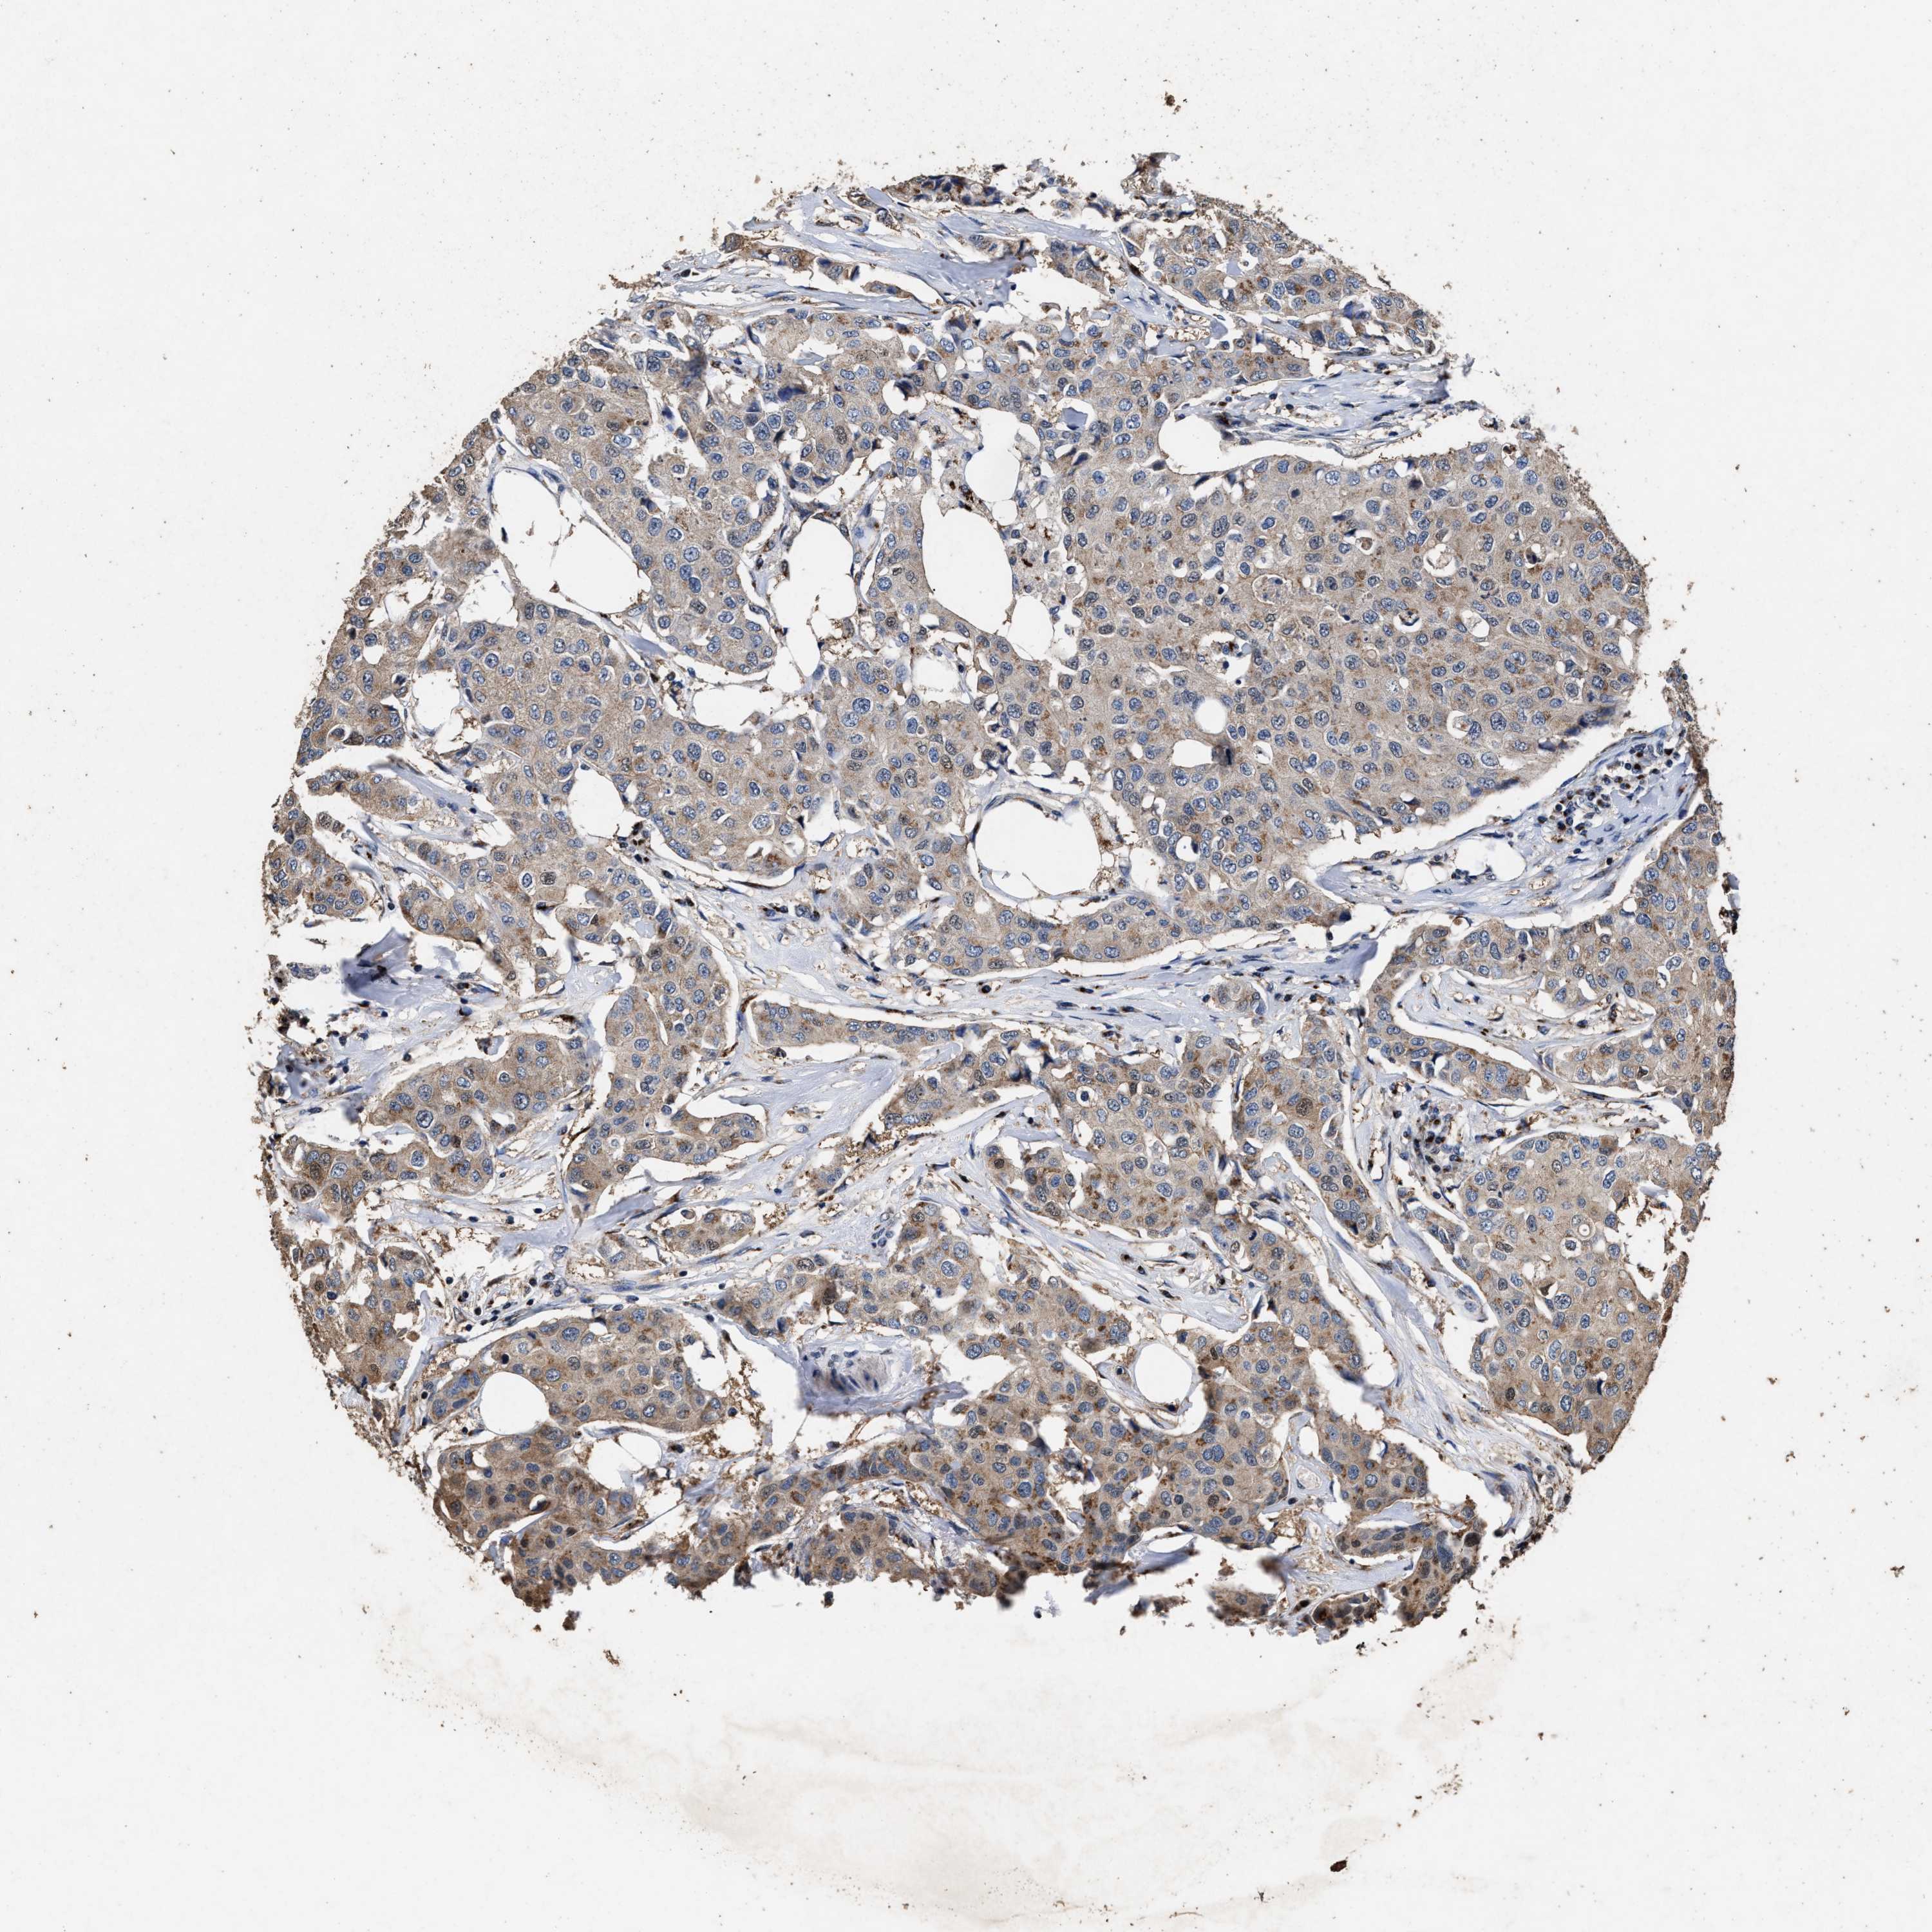

CANCER BREAST CANCER Show tissue menu

BRCA TCGA BRCA VALIDATION PROTEIN EXPRESSION

Breast cancer

Human cancer

TPST2 is not prognostic in Breast Invasive Carcinoma (TCGA)